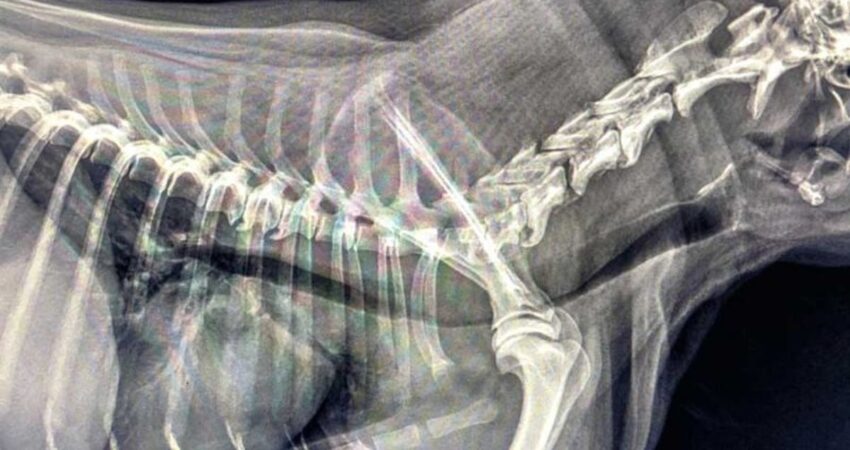

Zapadanie tchawicy u psów (TCS-Tracheal Collapse Syndrome) jest przewlekłą chorobą układu oddechowego obserwowaną głównie u raz małych i miniaturowych (Yorkshire terrier, Szpic miniaturowy, Chihuahua). Choroba ta polega na „zapaści” tchawicy co w znacznym stopniu ogranicza jej drożność. Odnotowuje się dwa procesy przyczyniające się do rozwoju tej choroby. Pierwszy z nich, najbardziej klasyczny, to dynamiczna obstrukcja dróg oddechowych, spowodowana chondromalacją i osłabieniem mięśni tchawiczych. Drugi proces, to statyczna obstrukcja związana z malformacją chrząstek tchawiczych i ich układem przypominającym literę „W”.